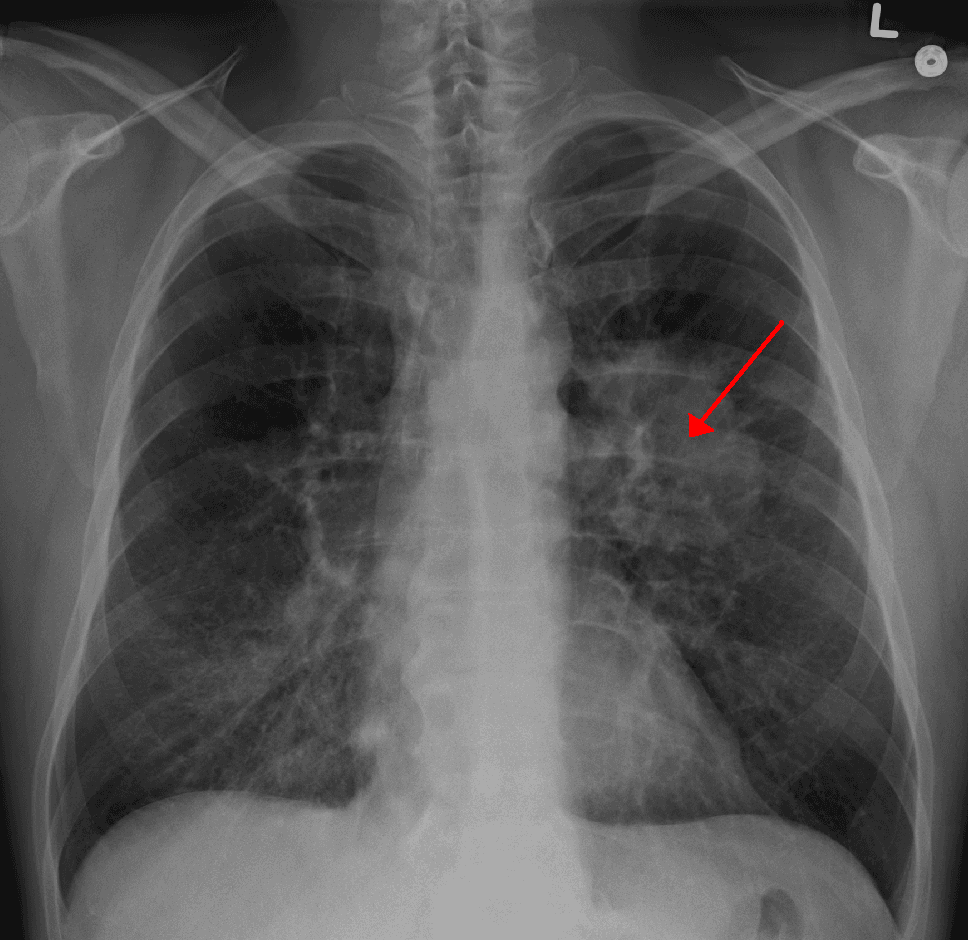

Lung cancer, also known as lung carcinoma, is a malignant tumor that begins in the lung. Lung cancer is caused by genetic damage to the DNA of cells in the airways, often caused by cigarette smoking or inhaling damaging chemicals. Damaged airway cells gain the ability to multiply unchecked, causing the growth of a tumor. Without treatment, tumors spread throughout the lung, damaging lung function. Eventually lung tumors metastasize, spreading to other parts of the body. Early lung cancer often has no symptoms and can only be detected by medical imaging. As the cancer progresses, most people experience nonspecific respiratory problems: coughing, shortness of breath, or chest pain. Other symptoms depend on the location and size of the tumor. Those suspected of having lung cancer typically undergo a series of imaging tests to determine the location and extent of any tumors. Definitive diagnosis of lung cancer requires a biopsy of the suspected tumor be examined by a pathologist under a microscope. In addition to recognizing cancerous cells, a pathologist can classify the tumor according to the type of cells it originates from. Around 15% of cases are small-cell lung cancer, and the remaining 85% (the non-small-cell lung cancers) are adenocarcinomas, squamous-cell carcinomas, and large-cell carcinomas. After diagnosis, further imaging and biopsies are done to determine the cancer's stage based on how far it has spread. Treatment for early stage lung cancer includes surgery to remove the tumor, sometimes followed by radiation therapy and chemotherapy to kill any remaining cancer cells. Later stage cancer is treated with radiation therapy and chemotherapy alongside drug treatments that target specific cancer subtypes. Even with treatment, only around 20% of people survive five years on from their diagnosis. Survival rates are higher in those diagnosed at an earlier stage, diagnosed at a younger age, and in women compared to men. Most lung cancer cases are caused by tobacco smoking.